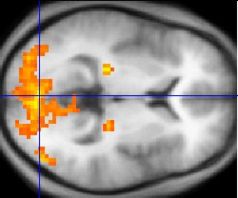

fMRI and PET

Functional magnetic resonance imaging (fMRI) measures changes in blood flow in the brain, but the activity of neurons is not directly measured, nor can it be distinguished whether this activity is inhibitory or excitatory. fMRI is a noninvasive, indirect method for measuring neural activity that is based on BOLD; Blood Oxygen Level Dependent changes. The changes in blood flow that occur in capillary beds in specific regions of the brain are thought to represent various neuronal activities ( metabolism of synaptic reuptake). Similarly, a positron emission tomography (PET), is able to monitor glucose and oxygen metabolism as well as neurotransmitter activity in different areas within the brain which can be correlated to the level of activity in that region.